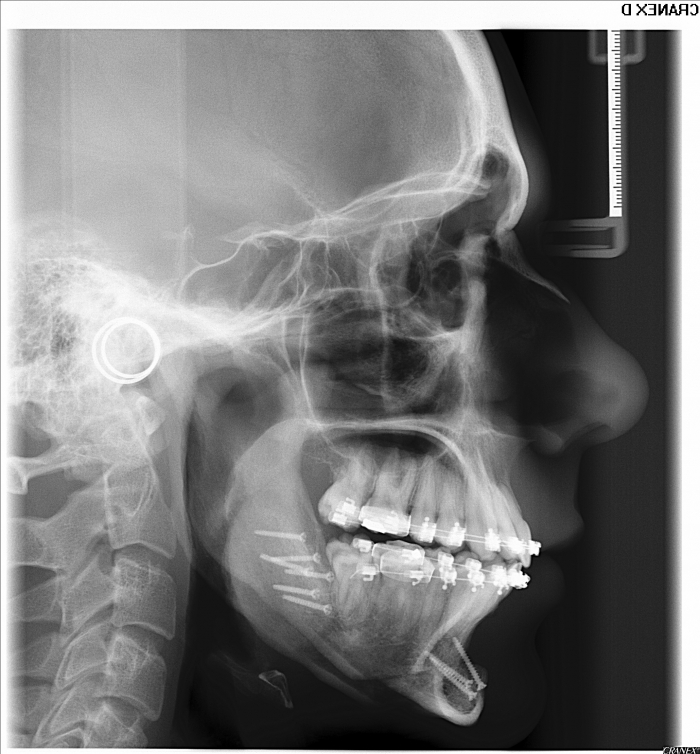

Telerradiografia perfil após cirurgia realizada em 2015 - Clínica Cliniface

Telerradiografia perfil após cirurgia realizada em 2015